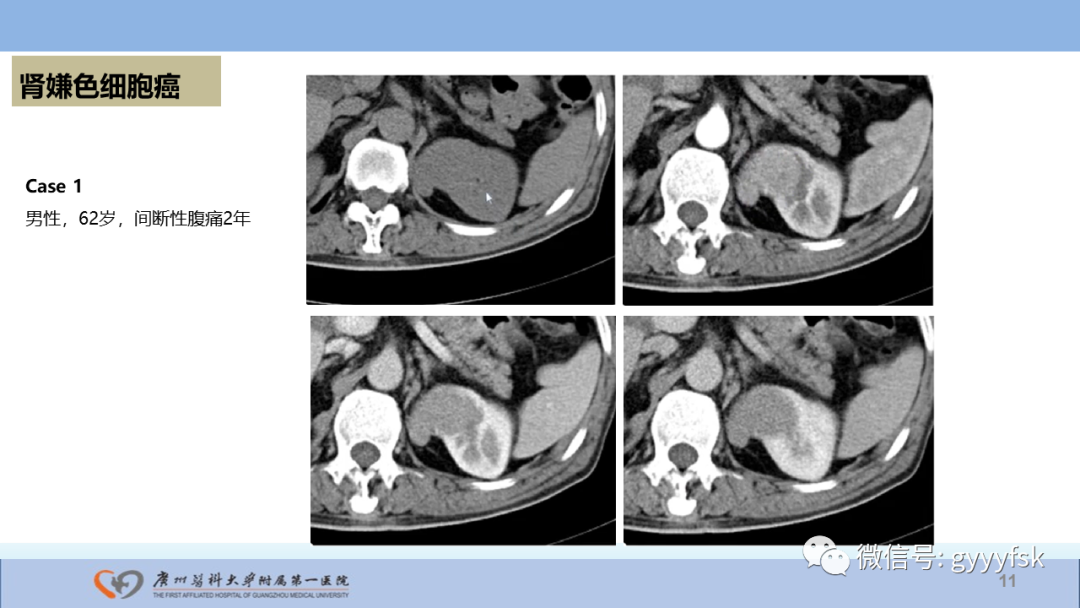

【PPT】肾癌相关影像诊断的文献汇报-11